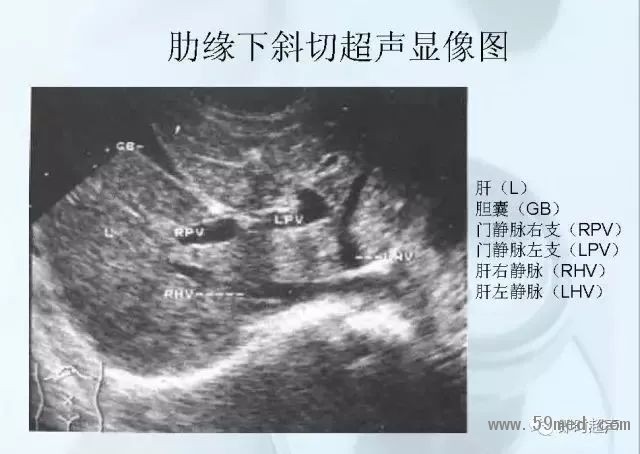

新聞中心 收藏!正常B超解剖圖譜,超實用!

![]() ![]() ![]() ![]() ![]() ![]() ![]() ![]() ![]() ![]() ![]() ![]() ![]() ![]() ![]() ![]() ![]() ![]() ![]() ![]() ![]() ![]() ![]() ![]() ![]() ![]() ![]() ![]() ![]() ![]() ![]() ![]() ![]() ![]() ![]() ![]() ![]() 【注:本文來源于即時超聲,版權(quán)歸原作者所有,如有侵權(quán) 請聯(lián)系 速刪】 =========================== 【閱精彩*悅分享】隨手點擊轉(zhuǎn)至朋友圈,與大家一起分享精彩資訊!當(dāng)然您也可以通過以下方式找到我,與您共同分享藍(lán)韻影像超聲的更多精彩!微信號:landultrasound 電話:+86-0755-66869896 24小時客服熱線:400-888-6452